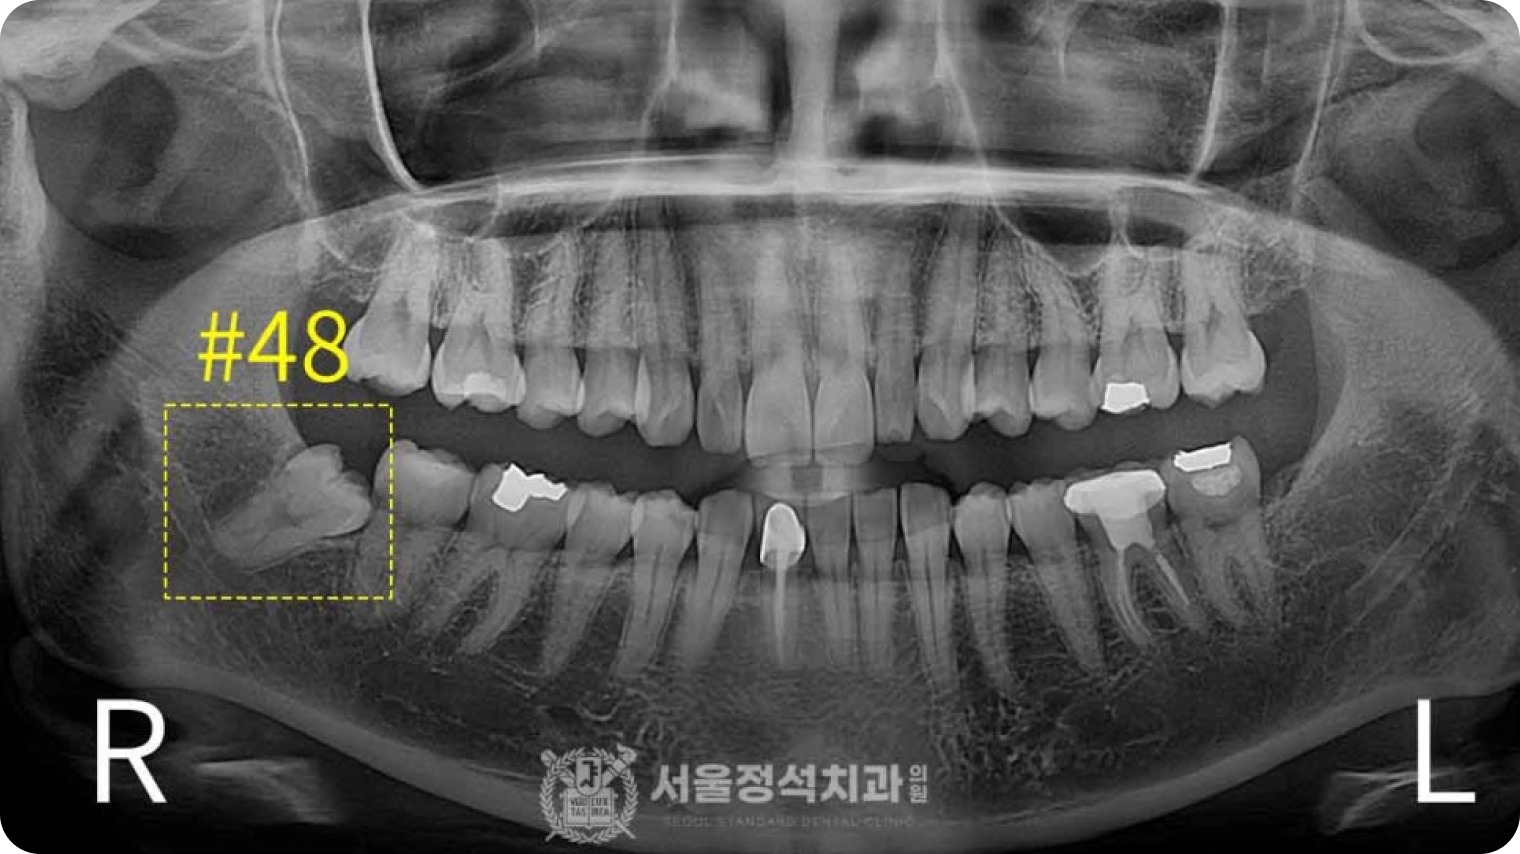

당일 사랑니 발치

당일 사랑니 발치

당일 사랑니 발치

사랑니는 영구치열을 방해하고 관리가 어려워 충치, 염증 등 문제를 일으킵니다. 신경까지 고려하는 당일 사랑니 발치로 빠르고 안전하게 해결합니다.